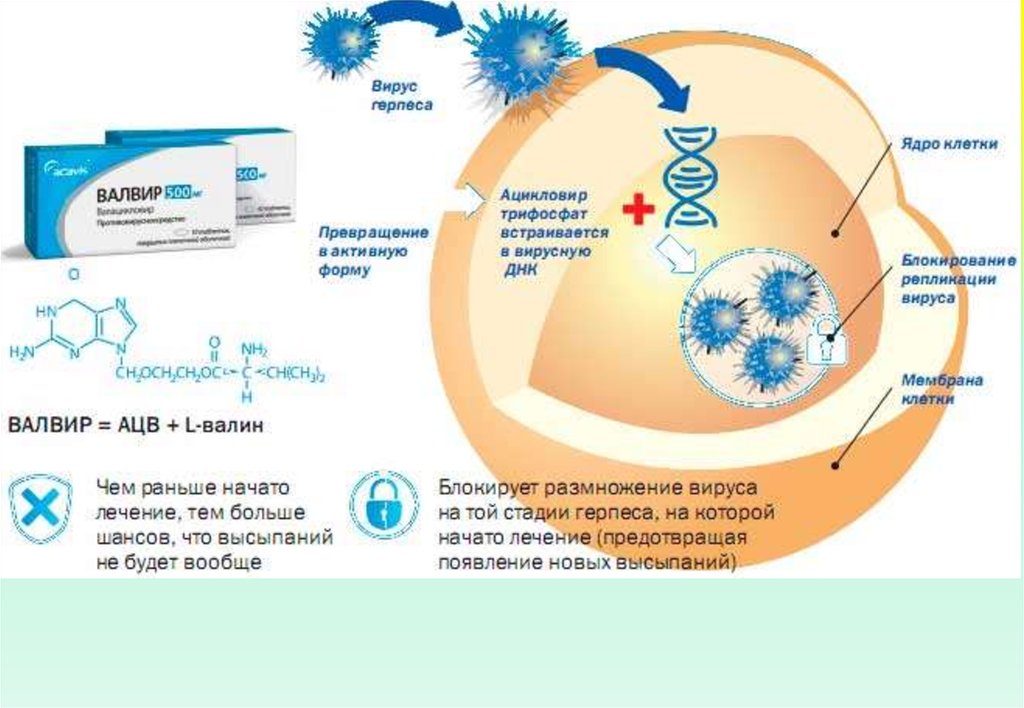

Медицинские снимки и изображения опоясывающего герпес вируса

Раздел: Фотодневник открытий